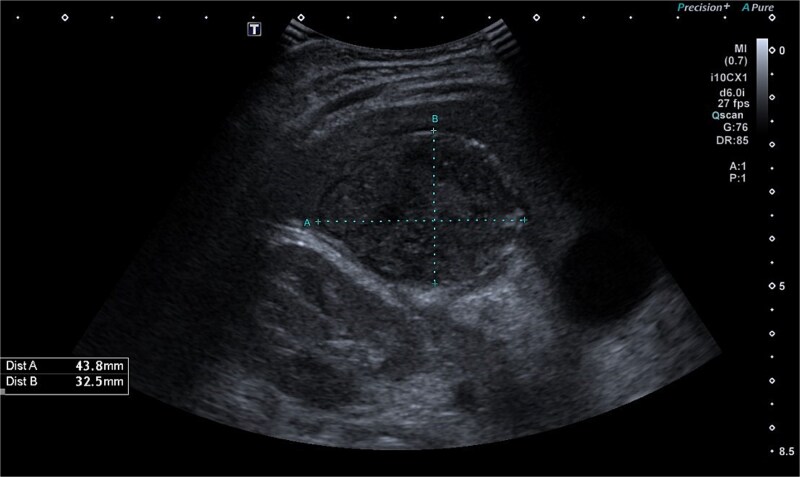

摘要肝下脓肿是急性阑尾炎的罕见并发症,常因诊断迟缓及表现不典型而引起。我们报告的情况下,一个3岁的男性表现发烧和腹痛,后来诊断为肝下脓肿继发于急性阑尾炎。腹部影像学显示多发脓肿,包括原发性肝下脓肿邻近肝V节和肝VI节,盲肠后炎性阑尾伴阑尾炎。患者接受抗生素治疗,开腹,引流肝下脓肿,切除坏疽阑尾。手术探查发现炎性粘连累及十二指肠和邻近的肠道结构,我们对其进行了精心的解剖和处理。这个病例强调了高度临床怀疑和及时成像的重要性,儿科患者急性阑尾炎的不典型表现。

Subhepatic abscesses are rare complications of acute appendicitis, often caused by delayed diagnosis and atypical presentation. We report the case of a 3-year-old male presenting with fever and abdominal pain, later diagnosed with a subhepatic abscess secondary to acute appendicitis. Abdominal imaging revealed multiple abscesses, including a primary subhepatic abscess adjacent to liver segments V and VI, and a retrocecal inflamed appendix with an appendicolith. The patient was treated with antibiotics and underwent laparotomy, drainage of the subhepatic abscess, and removal of a gangrenous appendix. Surgical exploration revealed inflammatory adhesions involving the duodenum and adjacent intestinal structures, which were meticulously dissected and managed. This case underscores the importance of high clinical suspicion and timely imaging in pediatric patients with atypical presentations of acute appendicitis.